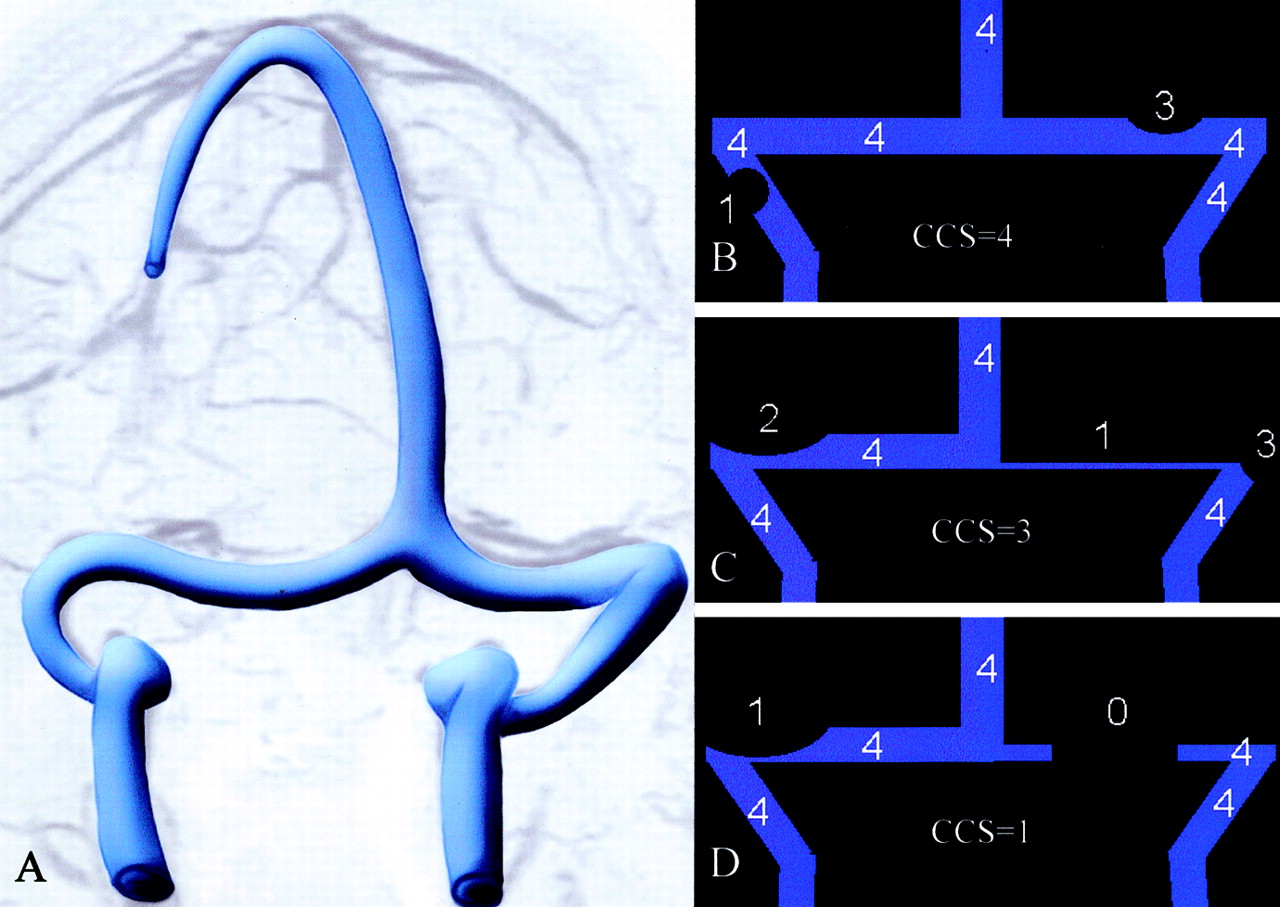

图6。ATECO vs TOF MRV。(一)老挝和(B)拉奥分段最大强度投影(MIPs) ATECO MRV的控制病人展示良好的可视化的右(箭头)和左(打开箭头)横向和乙状窦。注意缺乏artifactual信号损失。(C和D)相应oblique-segmented MIPs从TOF MRV在同一病人获得先生在同一考试。注意信号的大量artifactual损失近端右横窦(弯曲的箭头)和最左横窦(箭头)。